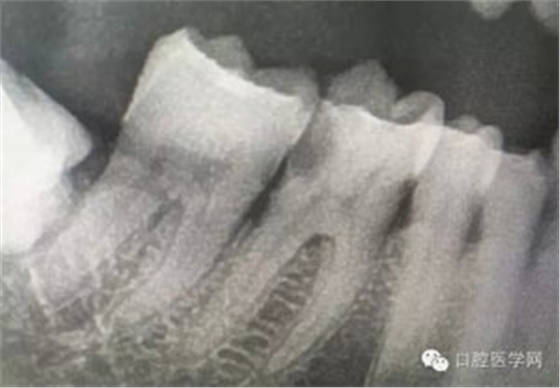

病例1:患者迫切希望保留自己的這一顆牙齒,根尖周陰影比較大,二度松動(dòng).而且旁邊有種植修復(fù)體,和患者溝通好后,治療好后觀察一個(gè)月后冠修復(fù),因?yàn)橛蟹N植的后期修復(fù),所以有了機(jī)會(huì)觀察,術(shù)后三個(gè)月和術(shù)后四個(gè)月,根尖恢復(fù)的還算不錯(cuò),希望能夠繼續(xù)觀察下去.這樣子的病例,做的時(shí)候我們一定要非常的小心,和患者要有充分的溝通以及不同科室的溝通然后決定怎么樣做比較好,假如就是出現(xiàn)了問(wèn)題,到時(shí)候我們也比較好處理些,免得我們自己到時(shí)候不好收?qǐng)觥?/span> 病例2:364647中齲的樹(shù)脂充填,現(xiàn)在樹(shù)脂的充填材料非常之多,有些時(shí)候,我們感覺(jué)有了好的材料我們就可以做出好的修復(fù),可是這是在我們有扎實(shí)的基本功的基礎(chǔ)上的,我們可以沒(méi)有那么好的樹(shù)脂,那么多的顏色選擇,修復(fù)的那么的逼真,但是我們至少要恢復(fù)患者牙齒的功能,將腐質(zhì)去除干凈,薄壁弱尖消除掉,選擇好適應(yīng)癥,給患者以盡可能好的修復(fù)。 來(lái)源于KQ88